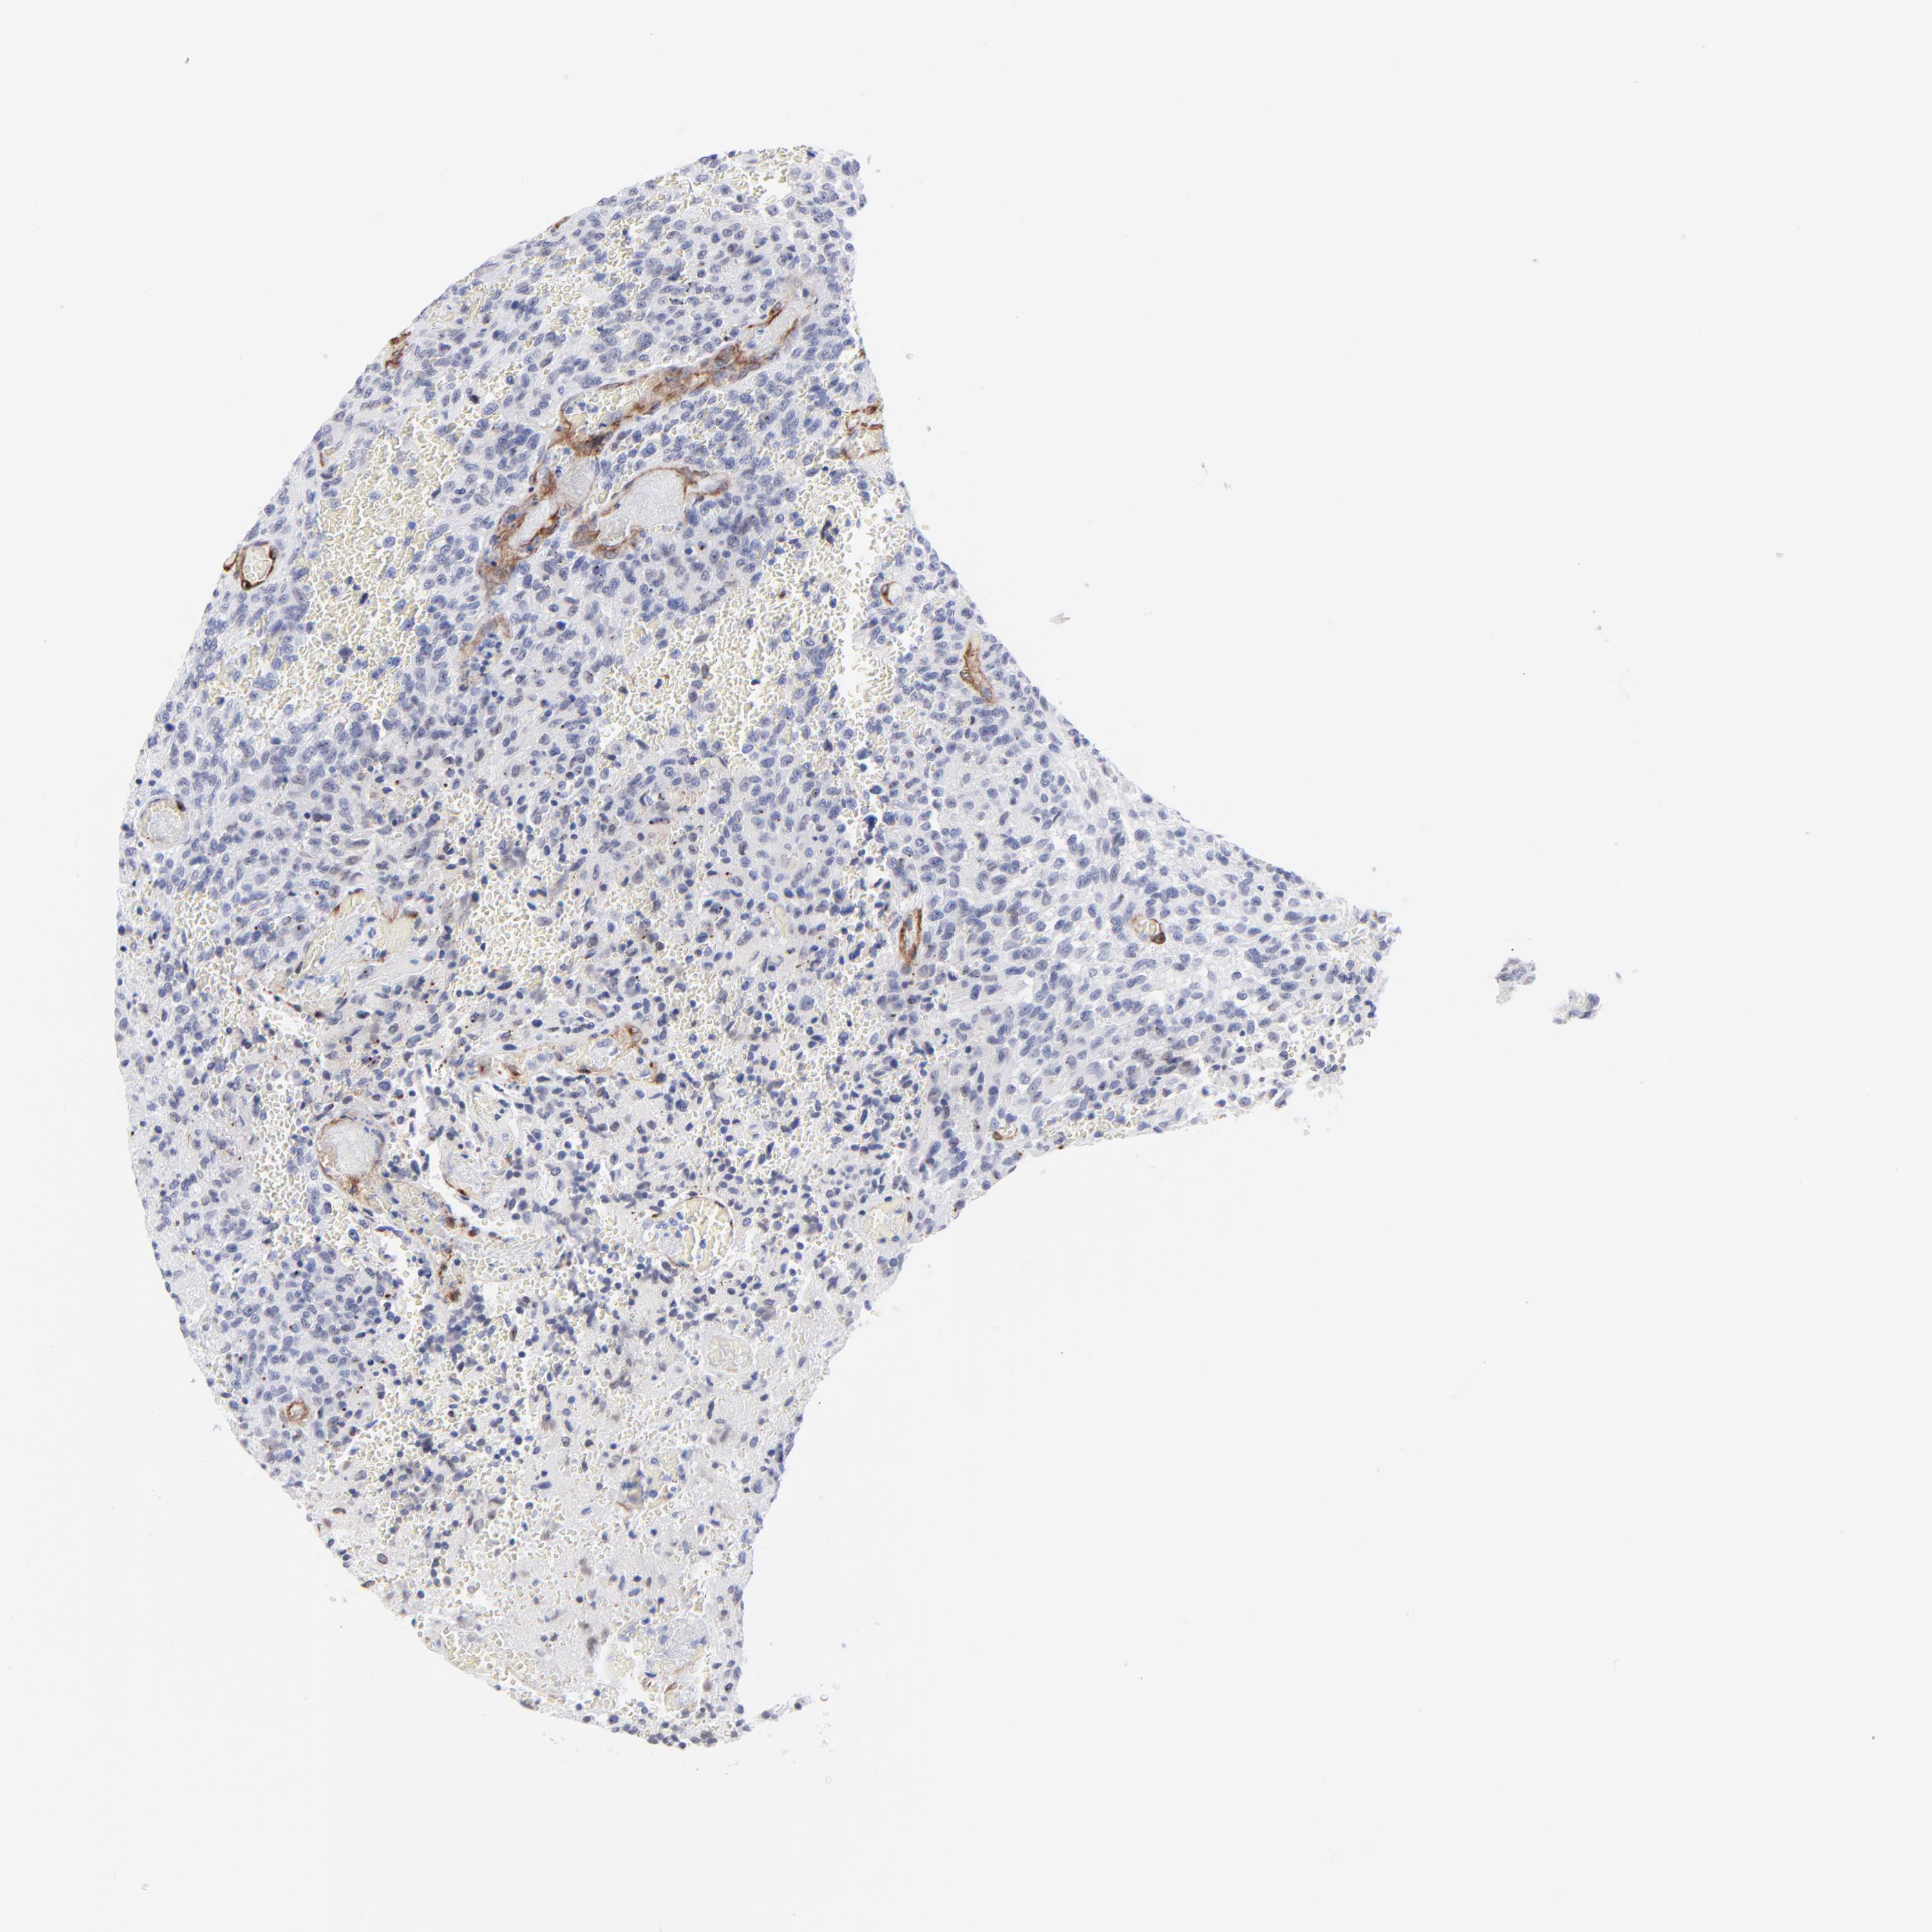

GLIOMA - Protein expressioni

A mouse-over function shows sample information and annotation data. Click on an image to view it in a full screen mode. Samples can be filtered based on level of antibody staining by selecting one or several of the following categories: high, medium, low and not detected. The assay and annotation is described here.

Note that samples used for immunohistochemistry by the Human Protein Atlas do not correspond to samples in the TCGA dataset.

Antibody stainingi

Antibody staining in the annotated cell types in the current human tissue is reported as not detected, low, medium, or high, based on conventional immunohistochemistry profiling in selected tissues. This score is based on the combination of the staining intensity and fraction of stained cells.

Each image is clickable and will lead to virtual microscopy that enables deeper exploration of all samples and also displays staining intensity scores, fraction scores and subcellular localization as well as patient and tissue information for each sample.

Antibody CAB003842

Antibody CAB018144

Staining

High

Medium

Low

Not detected

Intensity

Strong

Moderate

Weak

Negative

Quantity

>75%

75%-25%

<25%

None

Location

Nuclear

Cytoplasmic/membranous

Cytoplasmic/membranous,nuclear

Glioma, malignant, High grade

Glioma, malignant, NOS

Glioma, malignant, Low grade